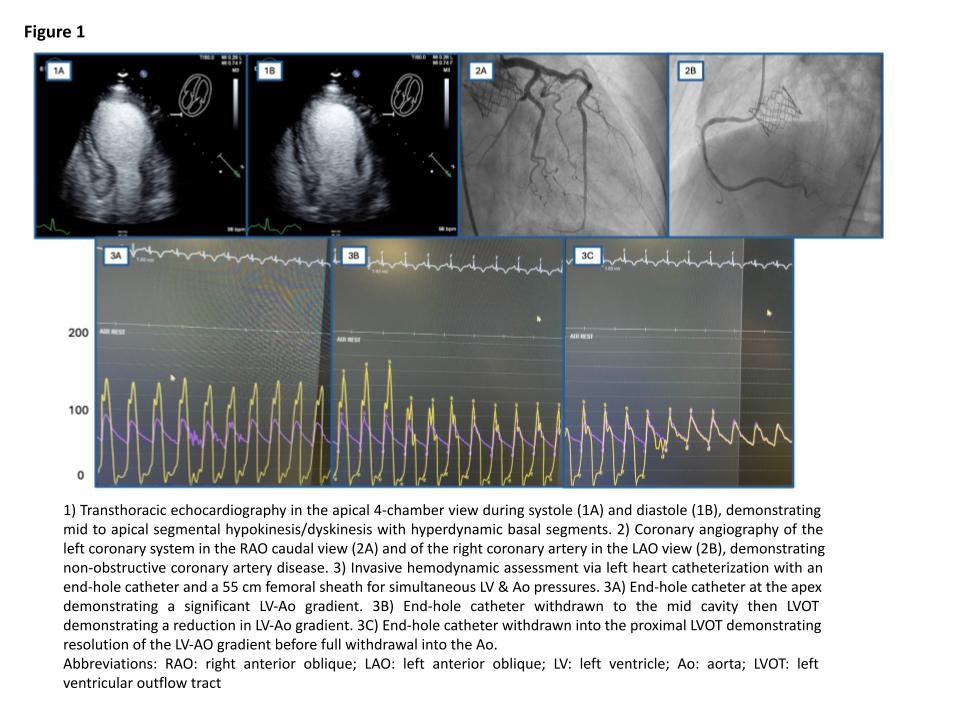

A 63-year-old woman with nonischemic cardiomyopathy (CM) with recovered ejection fraction (EF), severe bicuspid aortic valve (AV) stenosis post-transcatheter aortic valve replacement (TAVR) and prior methamphetamine use presented with chest pain, troponin >6000 ng/L, and anterolateral (V2-V6) ST elevation, T wave inversion, and Q waves. She was transferred for possible late or completed STEMI. Echocardiogram showed reduced ejection fraction (25% from 55%), mid-apical wall akinesis to dyskinesis, and a hyperdynamic base. Continuous wave doppler through the AV revealed a mean gradient of 44 mmHg (previously 11 mmHg) raising concern for valve dysfunction.

Coronary angiography revealed nonobstructive coronary artery disease. Left heart catheterization via a 55 cm femoral sheath using an end-hole catheter with slow pullback in the left ventricle (LV) demonstrated a significant LV-aortic gradient at the apex that progressively diminished and resolved near the left ventricular outflow tract (LVOT) below the aortic valve, confirming dynamic LVOT obstruction.

The dynamic LVOT obstruction in this case resulted from hyperdynamic basal contraction against an akinetic apex, causing mid-cavity collapse and a falsely elevated transvalvular gradient, mimicking prosthetic valve stenosis. This underrecognized mechanism can mislead post-TAVR assessments, especially in the setting of catecholamine excess or myocardial inflammation. Initial concern for valve failure or infarction was redirected by invasive hemodynamics and multimodal imaging. Recognition of this physiology avoided unnecessary intervention and guided therapy.